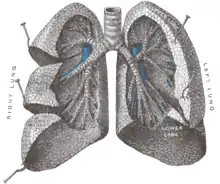

Lung Anatomy

Lung Anatomy

- Lungs: Right and Left

- Lobes:

- Right Lung: Right Upper Lobe (RUL), Right Middle Lobe (RML), Right Lower Lobe (RLL). Separated by oblique fissure and horizontal fissure

- Left Lung: Left Upper Lobe (LUL), Left Lower Lobe (LLL). Separated by oblique fissure. Lingula corresponds anatomically to RML, but is part of the LUL